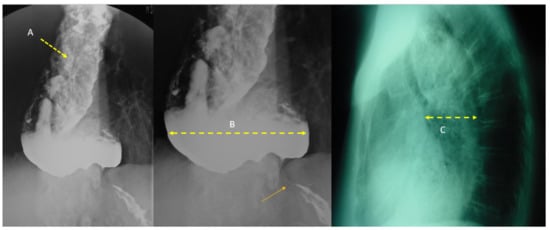

| Findings Found on Computed Tomography. | |

|---|---|

| Grade 1 | Homogenous enhancement of the esophageal wall while wall edema andmediastinal fat stranding are absent 1. |

| Grade 2a | Injuries display internal enhancement of the esophageal mucosa and hypodense aspect of the esophageal wall, which appears thickened while concomitant enhancement of the outer esophageal wall may sometimes confer a “target” aspect 2. |

| Grade 2b | Injuries present as a fine rim of external wall enhancement: the necrotic mucosa is not enhanced and fills the esophageal lumen, which indicates liquid density. Mediastinal fat stranding is uniformly present in grade 2 esophageal injuries. |

| Grade 3 | Transmural necrosis as shown by the absence of post-contrast wall enhancement 3. |